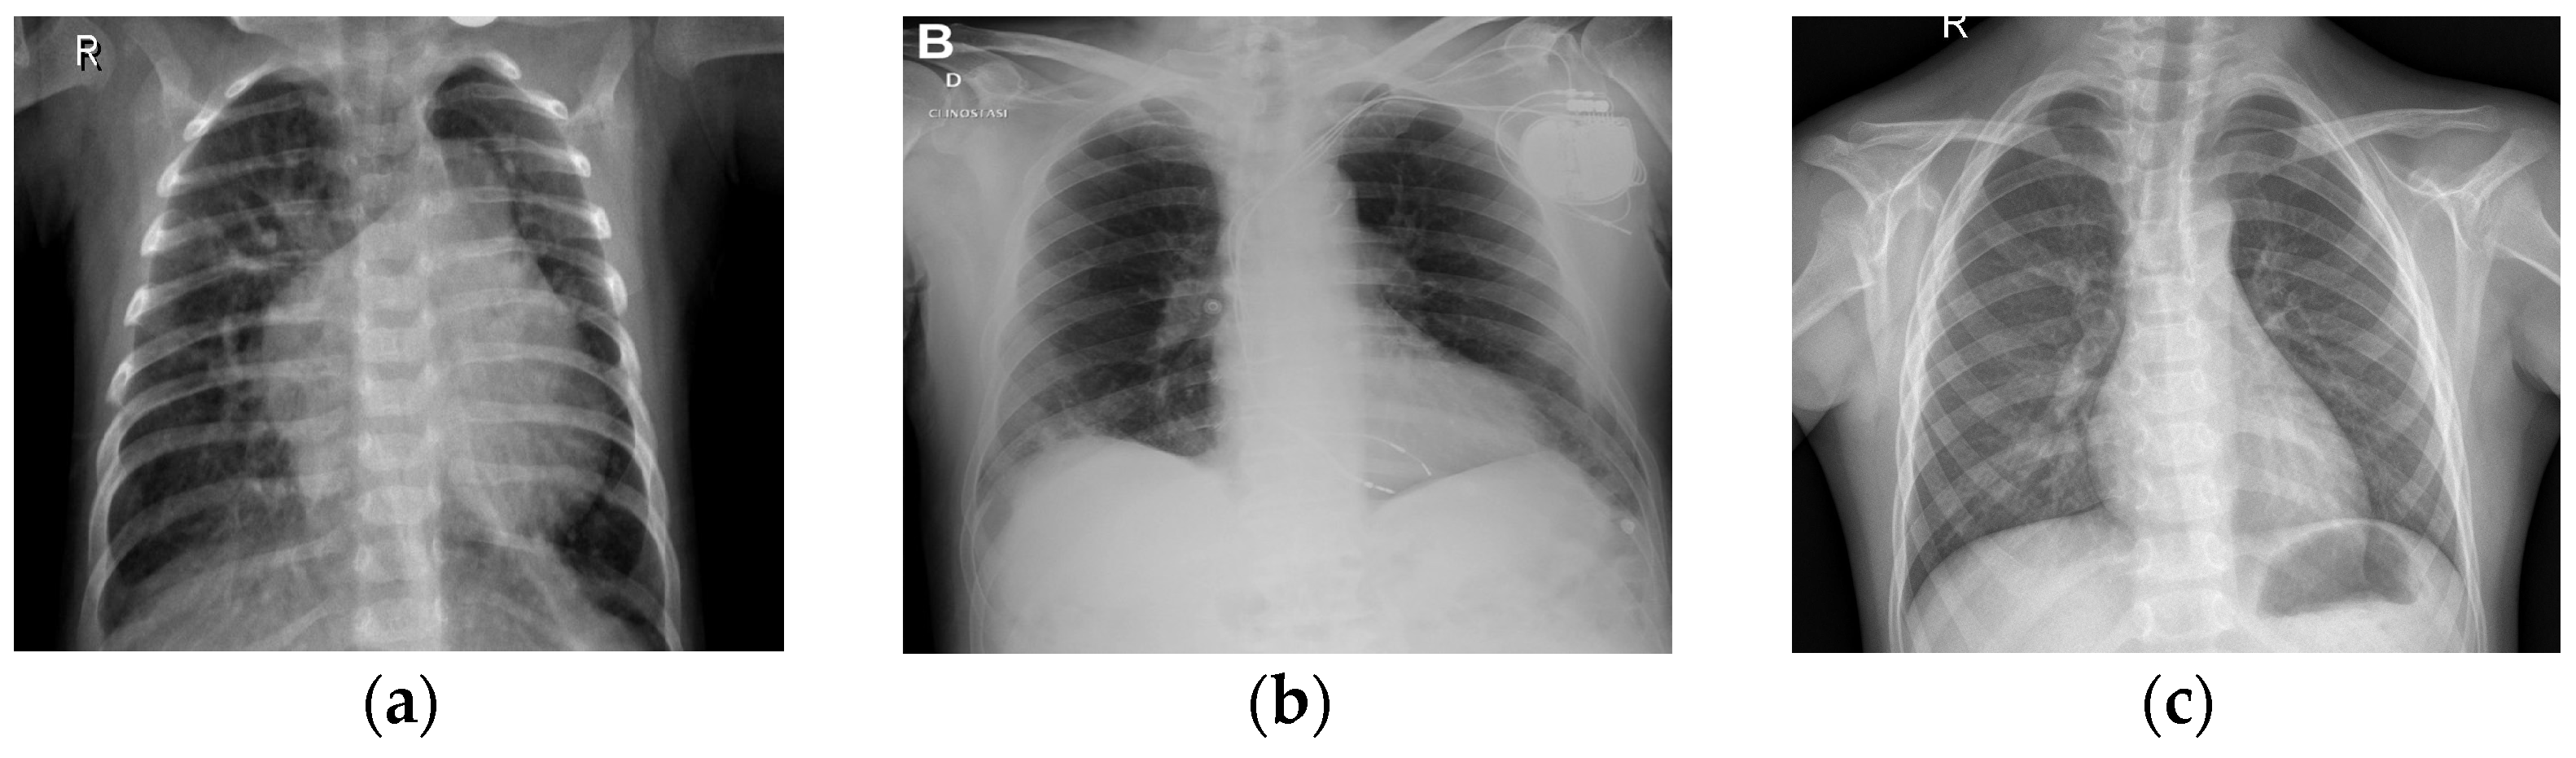

In Figure 2, it can be observed that EfficientNetB7 uses MBConv (Mobile Inverted Bottleneck Convolution) blocks with depth-wise separable convolutions, squeeze-and-excitation, and compound scaling to efficiently balance depth, width, and resolution for high-performance image classification. This figure features detailed information regarding the EfficientNetB7 architecture employed in the CXR-DNN model. The architecture is deconstructed into its fundamental layers and modules, with a particular emphasis on the advanced convolutional and MBConv blocks that improve the precision of feature extraction and classification. EfficientNetB7’s unique compound scaling and MBConv blocks with squeeze-and-excitation make it more efficient and accurate compared to other CNN models. Since Figure 1 and Figure 2 reflect varying degrees of information within the CXR-DNN model, they are linked. Presenting the whole model’s process from input to output, Figure 1 provides a macro-level perspective. Figure 2 offers a micro-level perspective, highlighting the EfficientNetB7 architecture which is fundamental for the step of feature extraction shown in Figure 1. Taken together, they offer a complete understanding of both the general framework and the complex operations of the model. Figure 1 supports the study by visually summarizing the methodology used for COVID-19 screening, making it easier for readers to grasp the end-to-end process. Figure 2 complements this by detailing the core architecture that underpins the model’s robust performance, thus emphasizing the technical innovation and depth of the proposed solution. This combination helps to clearly convey the significance of the research and its approach to achieving reliable COVID-19 diagnostics through advanced deep learning techniques. To illustrate further the differences in CXR images belonging to classes 1 (COVID-19), 2 (normal), and 3 (pneumonia), Figure 3 shows three examples of lung X-rays (one for each class).

Figure 3a shows a normal chest X-ray, which would reveal transparent lungs with no abnormalities. The consequence of suffering from COVID-19 is a fatal respiratory illness that causes severe breathing difficulties in both lungs (Figure 3b). The lungs may show patchy or consolidated opacities in a CXR with COVID-19 infection. When an infection strikes the lungs, it can lead to viral pneumonia (Figure 3c), which in turn leads to inflammation of the alveoli, the tiny air sacs in the lungs that are essential for exchanging oxygen and carbon dioxide, and which requires immediate medical advice or treatment. Coughing, fever, shortness of breath, chest pain, and exhaustion are all symptoms of pneumonia. Because of the inflammation, fluid may collect in the lungs, making it difficult to breathe. The best way to distinguish between COVID-19 and COVID-19 pneumonia is to consider them different steps of the same illness. COVID-19 is a respiratory sickness caused by SARS-CoV-2, and COVID Pneumonia is a complication of COVID-19 that causes the cited inflammation and fluid in the lungs [33]. There is reason for alarm with influenza, since it may lead to everything from a mild cold to pneumonia, acute respiratory distress syndrome, and even death.

Figure 3. CXR images of lungs in patients: (a) healthy, (b) COVID-19, and (c) pneumonia.